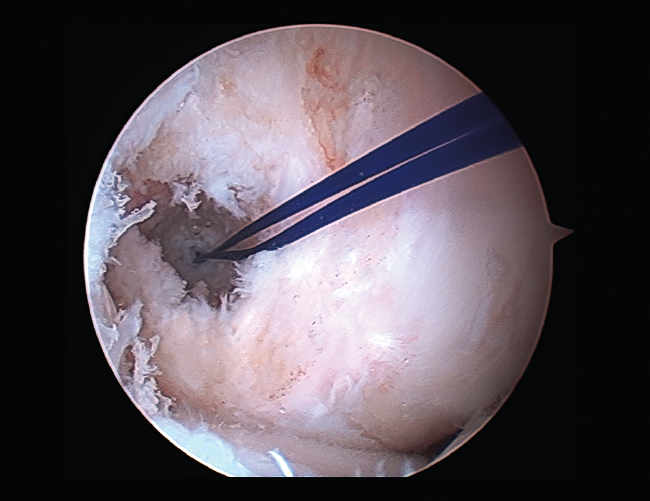

Rigidez

Una de las complicaciones más temidas, producida por un aumento del tejido fibroso, ya sea por la propia lesión (primaria) o secundaria a diferentes motivos (error técnico en la cirugía, síndrome del cíclope, inmovilización prolongada o la participación insuficiente en un programa de rehabilitación, infección, síndrome del dolor regional complejo, hematomas o sinovitis) (Figuras 7 y 8). Esta puede variar desde una ligera limitación del rango de movilidad hasta una severa artrofibrosis(21).

Figura 7. Adherencias intraarticulares.

Las principales causas secundarias a errores técnicos son la malposición de la plastia y el tensado excesivo. La radiografía permite ver la localización de los túneles e implantes, así como la RM visualiza las partes blandas implicadas, pudiendo identificar posibles pinzamientos de la plastia –escotadura intercondílea, síndrome del cíclope (Figura 9), síndrome de la contractura infrapatelar(22)(Figura 10)–.